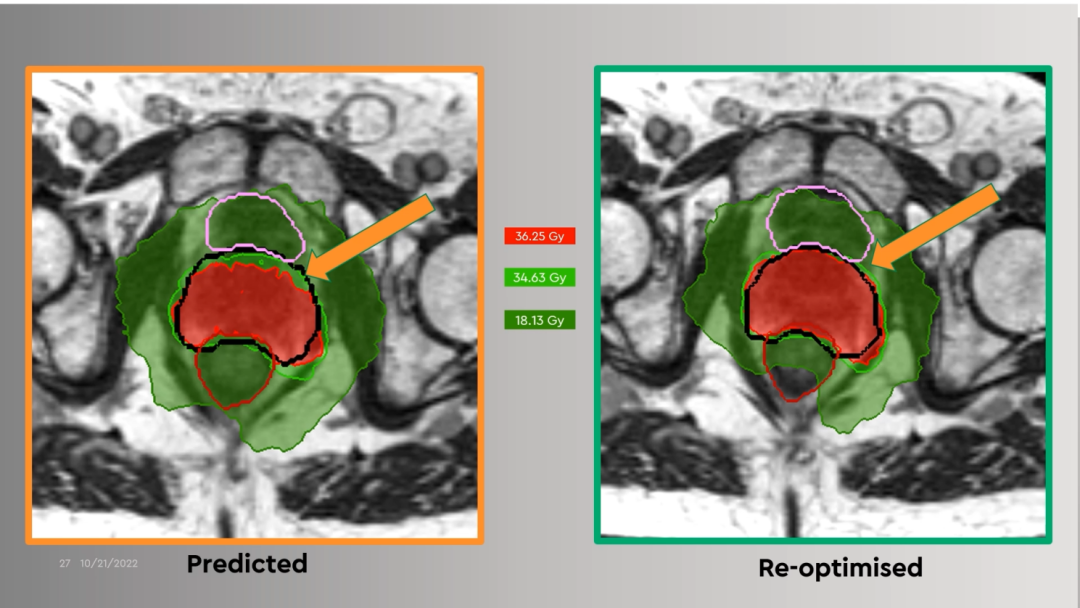

ǰÏßÏÙ°©·ÅÁÆÊ±ÈôʹÓÃÔÍýÏëµÄ¼ÁÁ¿ÂþÑÜ£¬£¬£¬£¬£¬£¬»áÓнϴóÇ·Á¿Çø£¬£¬£¬£¬£¬£¬¿ÉÒÔͨ¹ýMRIdianÔÚÏß×Ô˳ӦÓÅ»¯Ä£¿£¿£¿£¿£¿£¿£¿éÀû±ãµØ¸ÄÉÆÇ·Á¿¡£¡£¡£¡£¡£¡£¡£

Figure 16ǰÏßÏÙ°©·ÅÁÆÊ±ÈôʹÓÃÔÍýÏëµÄ¼ÁÁ¿ÂþÑÜ£¬£¬£¬£¬£¬£¬ÓнϴóÇ·Á¿Çø£¨×󣩣»£»£»£»£»£»£»£»ÔÚÏßÓÅ»¯ºóµÄ¼ÁÁ¿ÂþÑÜ£¬£¬£¬£¬£¬£¬ÎÞÇ·Á¿Çø£¨ÓÒ£©